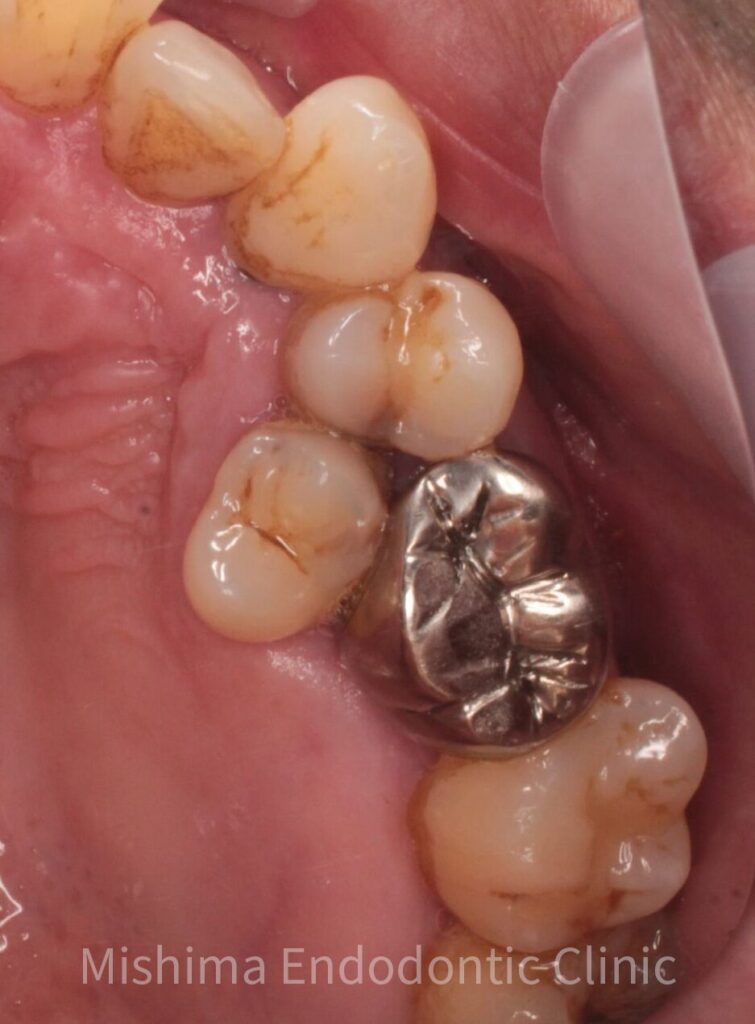

After

移植後1年